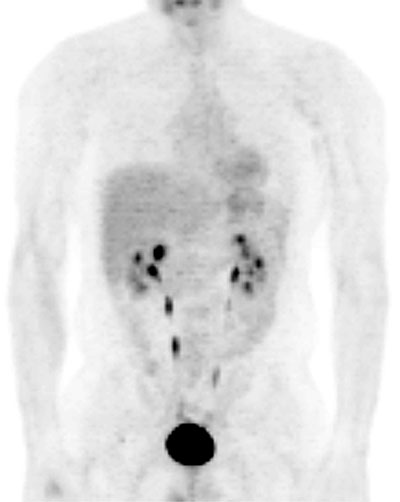

Fig. 18. - Imagen coronal de tomografía por emisión de positrones de cuerpo completo. Varón de 40 años sin antecedentes personales. Se aprecia la eliminación fisiológica de la [18]FDG en cálices y pelvis renales, ureteres y vejiga.